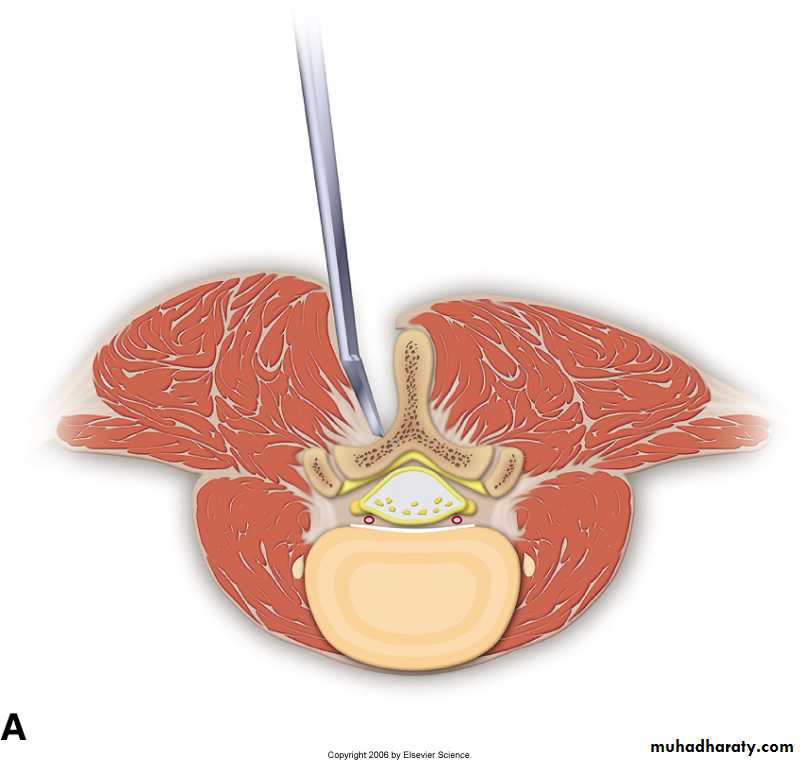

- open laminectomy with discectomy

- micro discectomy

Surgery